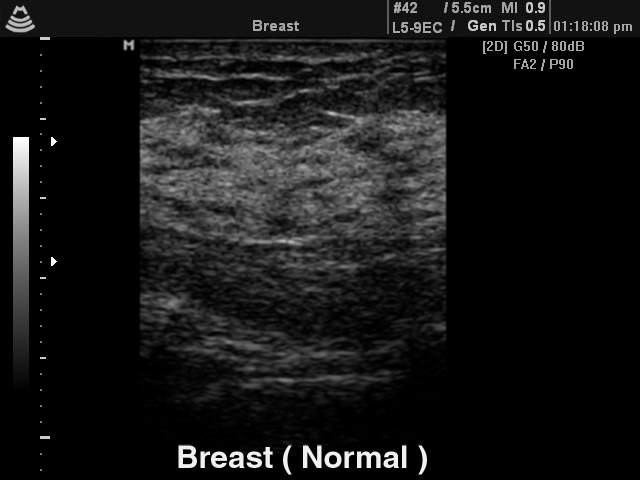

Breast - norm, B-mode

Breast - norm, B-mode (echogramm №144)

[RU] Ultrasound image №144: Breast (norm) in B-mode.

Echogramm was received by ultrasound scanner SonoAce-8000 (out of production).